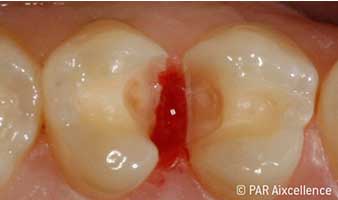

Рис. 4. Изображение, как на рис. 3, на этот раз с использованием Facelight